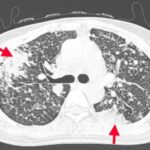

CASE LÂM SÀNG Điều trị bệnh nhân mắc đồng thời hai loại ung thư: Ung thư phổi và ung thư tuyến tiền liệt

CASE LÂM SÀNG Điều trị bệnh nhân mắc đồng thời hai loại ung thư: Ung thư phổi và ung thư...